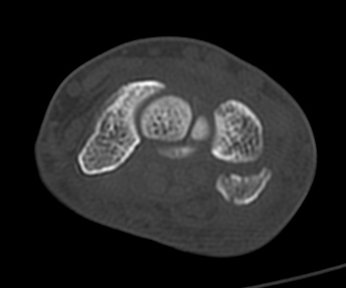

ÃÊÀ½ÆÄ°Ë»ç : ¼Õ¸ñ ¼ö±Ù°ü ±ÙÀ§ºÎ Ⱦ´Ü¸é°Ë»ç¿¡¼­ Äá¾Ë»À Ç¥ÃþÀ¸·Î ¾à°£ÀÇ ¿¬ºÎÁ¶Á÷ ºÎÁ¾ÀÌ °üÂûµÊ(»çÁø 1).